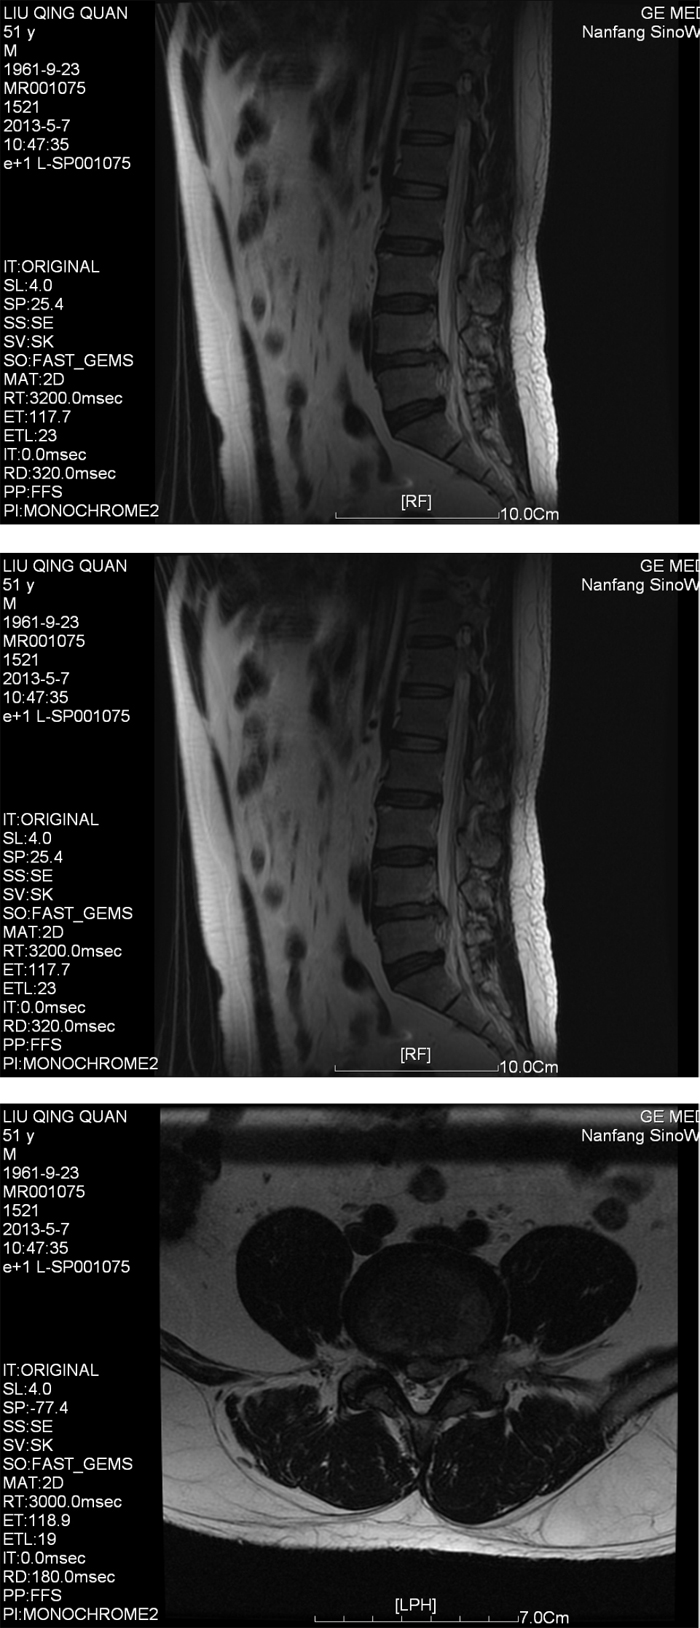

●南方医院腰椎CT及MRI检查提示:L4/5椎间盘右后型突出,压迫右侧神经根及硬脊膜囊。

●2013年5月患者搬重物后觉腰痛加重,次日晨起翻身困难,右小腿前下侧发麻,鞍区发麻,无大小便失禁。

●查体: L2-S1右侧椎间隙压痛及叩击痛(+),腰部活动受限,前屈30°。右下肢直腿抬高试验20°(+),加强实验(+),左下肢直腿抬高试验40°(+),加强实验(+),右下肢前外侧感觉稍减退。